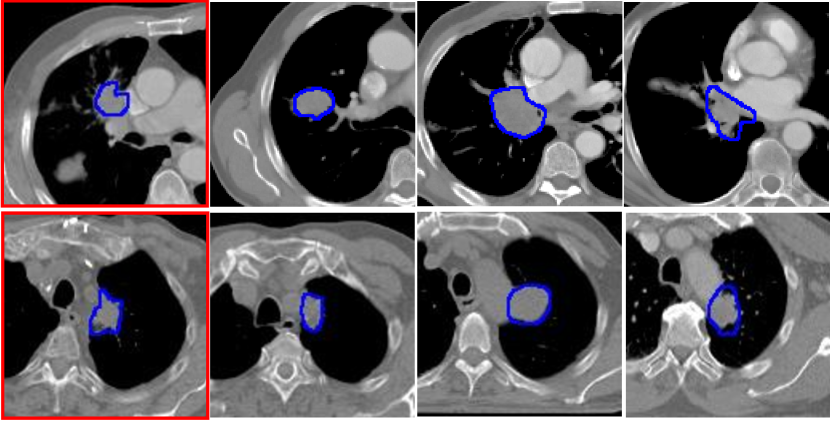

Fig. 2 shows LC segmentations generated by the analyzed methods for two representative examples. As shown, SMART as well as SMIT closely followed the expert delineation in the example cases despite the location of tumors abutting the mediastinum and adjacent to collapsed normal tissue. All other methods resulted in under- or over-segmentation.

Refer to caption

Figure 2: Representative LC segmentations produced by different methods.